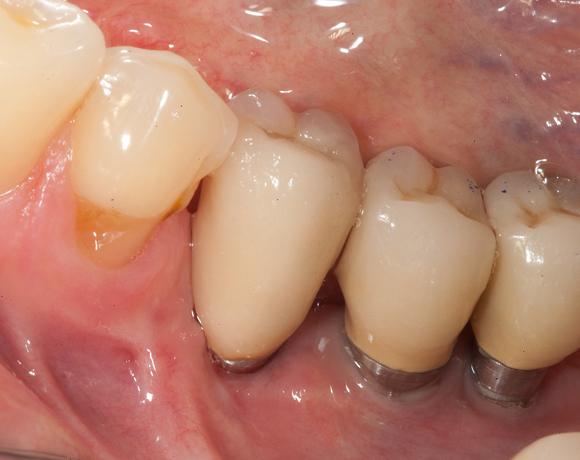

Knochenspaltung Unterkiefer 45 – 47

Im vorliegenden Fall war zwar eine gut Knochenhöhe vorhanden, jedoch war der Knochen zu schmal,

um Implantate aufzunehmen. Hier bietet es sich an den Knochen zu spalten, bei gleichzeitiger Insertion der Implantate und die freien Zwischenräume mit Kunstknochen aufzufüllen. Die Augmentation wird mit einer Membran abgedeckt. Die Einheilzeit beträgt sechs Monate.